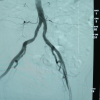

Kanamanın ancak bölgesini tespit edebilen doktorlar, cerrahi müdahale yapılamayacak kadar küçük olan bu alana anjiyo yöntemiyle yaklaşık 4 saatte ulaştı.

Anjiyo ile embolizasyon yöntemi kullanılarak, damar özel bir maddeyle tıkanıp operasyon tamamlandı.

Açık cerrahi ile tedavisinin mümkün olamayacağı için anjiyo yöntemini kullandıklarını belirten Kocaağa, "Kanamayı durdurmak işin kolay kısmı ancak tespit etmek zordu. Çünkü saç kadar ince bir damardan kanama oluyordu. Bütün damarları tek tek yakınlaştırıp mikro kateterle görüntüsünü aldık. Bunu tespit etmek yaklaşık 3,5 saatimizi aldı." dedi.

Uzman Dr. Fatih Rıfat Ulusoy ise anjiyo işlemini bu hastada damarı açmak için değil tıkamak amacıyla yaptıklarını kaydetti.

Müdahalenin ardından hastanın iyileşme sürecine girdiğini, bütün değerlerinin normale döndüğünü vurgulayan Ulusoy, "Bu hastamız için cerrahi şansımız yoktu. İlaçla da durduramadık. Tansiyonu düşmeye başlamıştı, şoka giriyordu. Tek çaremiz buydu ve hızlı şekilde görüntülemeyi yaparak kanamayı durdurduk. Hastamızın genel durumu gayet iyi. Sağ kalça kaslarını besleyen bir damar bu. Onun bu şekilde kanaması çok çok düşük bir ihtimal." diye konuştu.